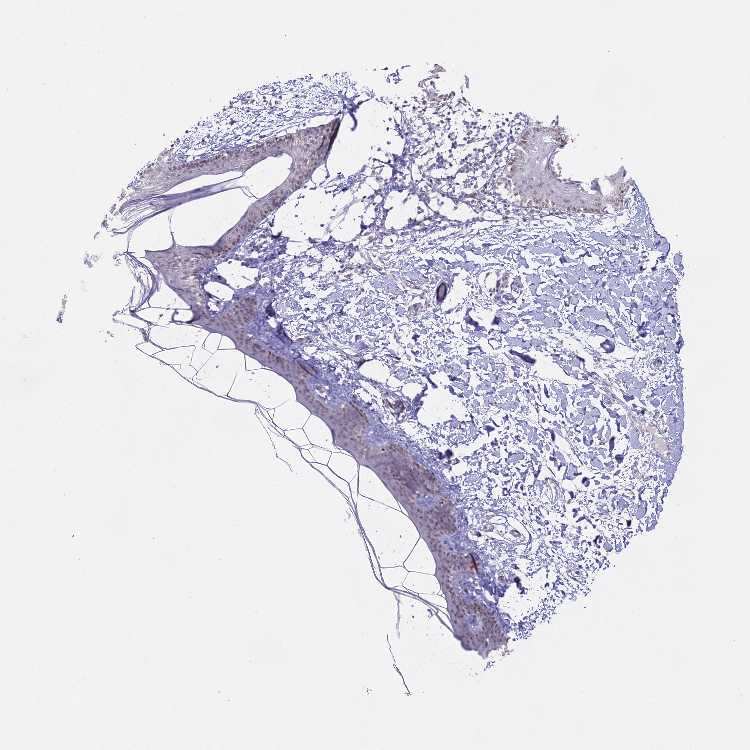

SKIN 1 - Antibody stainingi

Antibody staining in the annotated cell types in the current human tissue is reported as not detected, low, medium, or high, based on conventional immunohistochemistry profiling in selected tissues. This score is based on the combination of the staining intensity and fraction of stained cells.

Each image is clickable and will lead to virtual microscopy that enables deeper exploration of all samples and also displays staining intensity scores, fraction scores and subcellular localization as well as patient and tissue information for each sample.

Antibody HPA043028Antibody CAB009968

Langerhans Not detectedLow

Fibroblasts Not detectedNot detected

Keratinocytes LowLow

Melanocytes Not detectedMedium

SKIN 2 - Antibody stainingi

Epidermal cells MediumMedium